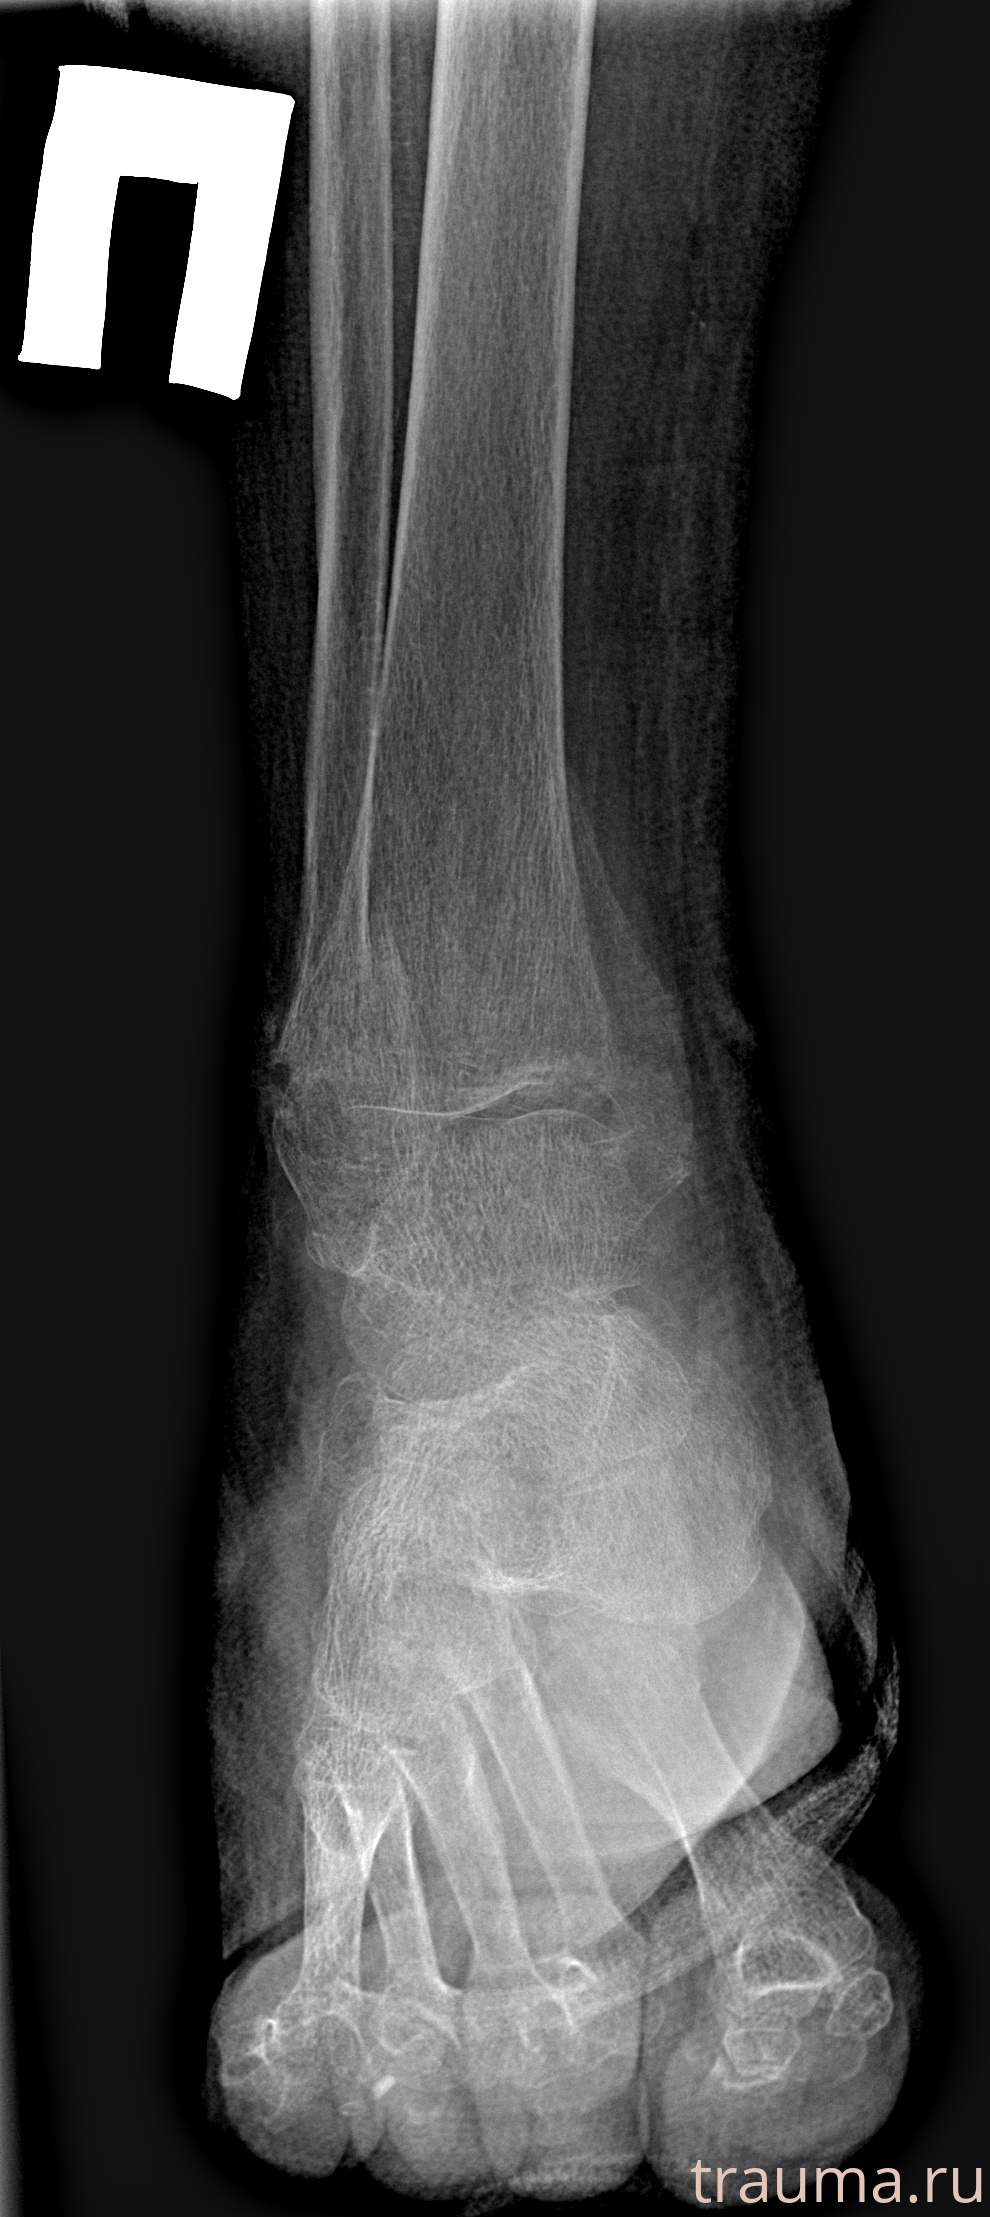

Рентген на дому: по вашему адресу приезжает врач-рентгенолог, травматолог-ортопед с мобильным рентгеновским аппаратом, проводит диагностику травмы или заболевания, делает необходимые рентгенограммы, дает рекомендации по дальнейшему лечению. Получить качественные снимки в домашних условиях возможно благодаря уникальной методике, разработанной МосРентген Центром для института  Склифосовского